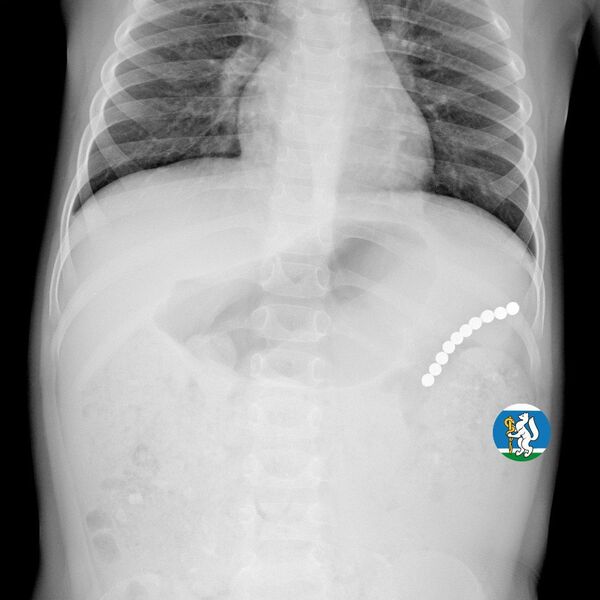

Девочка рассказала родителям о плохом самочувствии, и те показали ее врачам. Медики направили пациентку на рентген грудной клетки. Благодаря обследованию специалисты обнаружили в проекции желудка цепочку магнитов, соединенных между собой. Ребенку сразу же госпитализировали и оказали помощь.

«Для минимизации риска осложнений удаление инородных тел было проведено интраоперационно. В ходе вмешательства дежурная бригада врачей извлекла 10 магнитных шариков, цепочка которых в длину составила 5 сантиметров», — рассказал детский хирург ДГКБ №9 Андрей Чукреев.